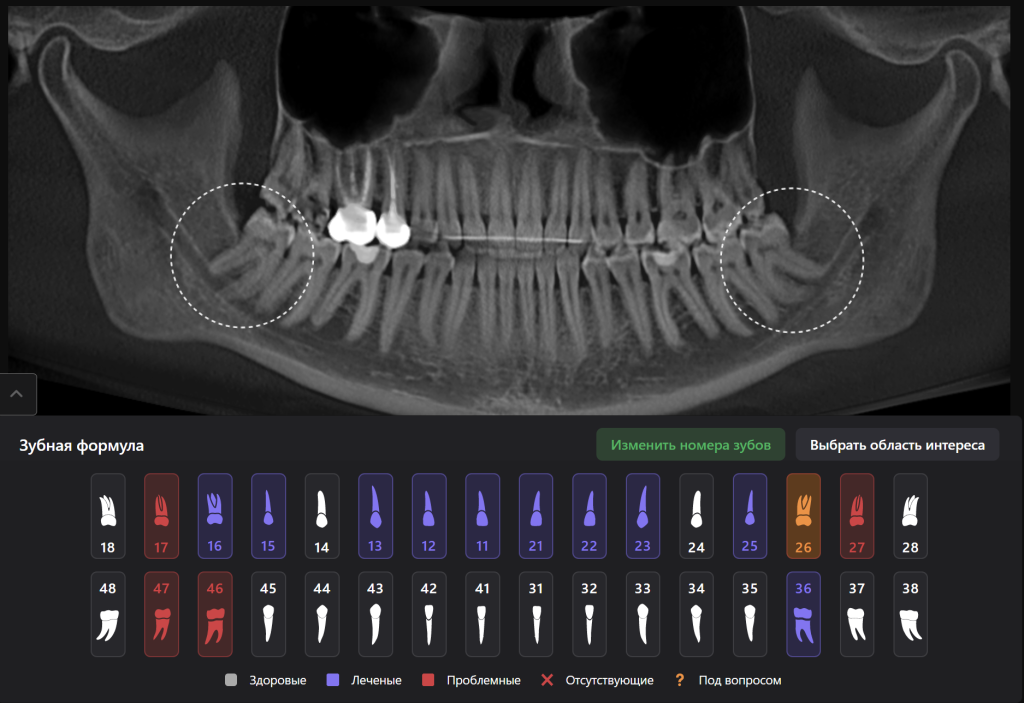

Diagnocat поможет Вам провести тщательное планирование удаления зубов 3.8 и 4.8, сводя риск возможных осложнений к минимуму

«Отчет по третьим молярам», созданный ИИ Diagnocat — это инструмент, который проводит точный трейсинг нижнечелюстного канала

И выстраивает оптимальную визуализацию в трех плоскостях и помогает врачу оценить расстояние до нижнечелюстного канала